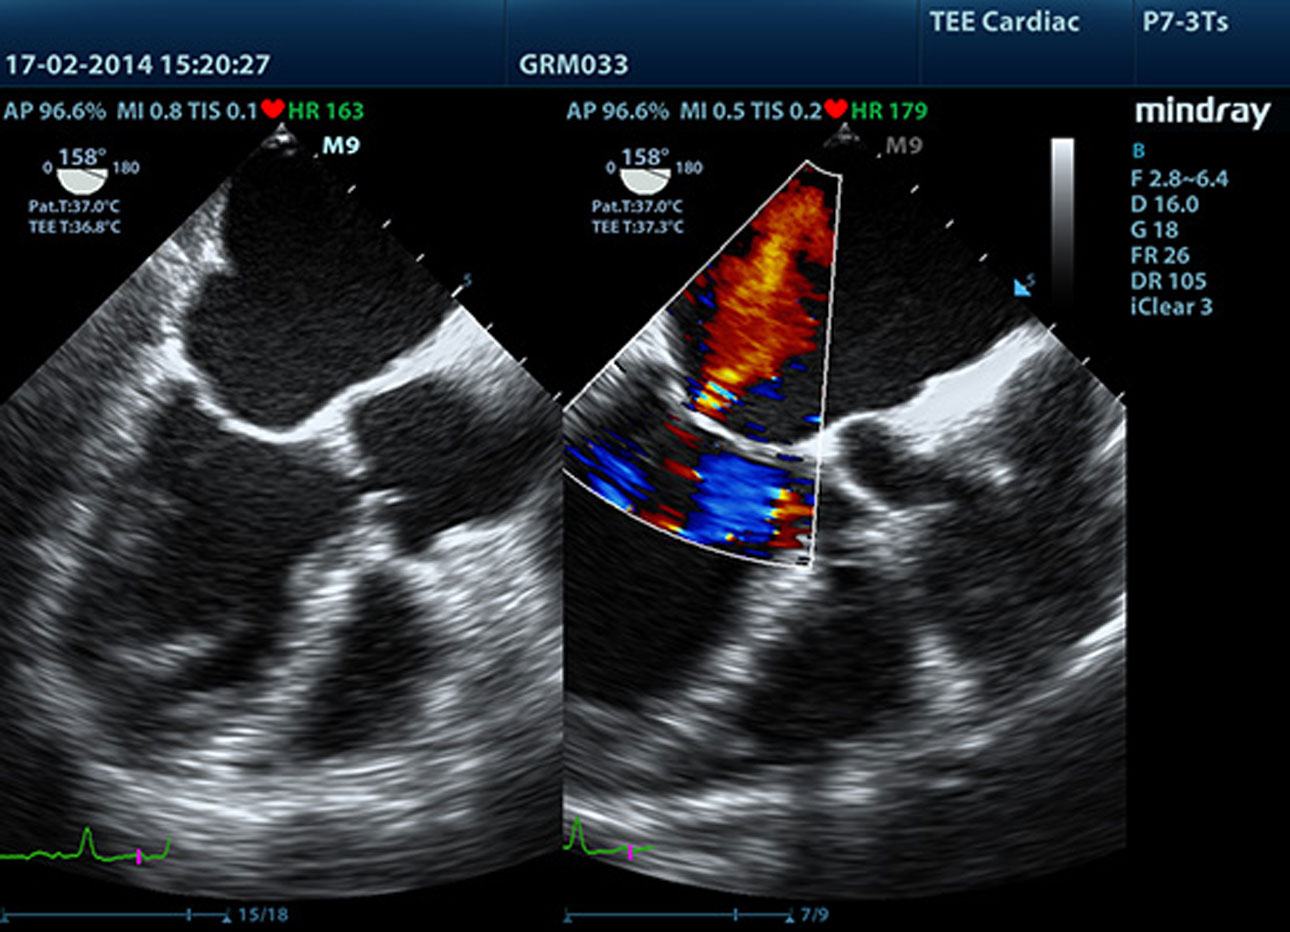

LVO with Stress Echocardiography

M9ŌĆÖs premium capabilities allow for LV opacification during stress, enhancing discrimination between myocardial tissue and blood pool, providing better visualisation of the endocardial surface. The Stress Echo feature on M9 includes a complete package for pharmacological stress and exercise stress echo. The package is supported by a flexible reporting system that can be optimised for your individual needs.

TDI

Tissue Doppler Imaging allows you to quantitatively evaluate local myocardial movement and function, providing complete TDI modes for faster and direct diagnoses.